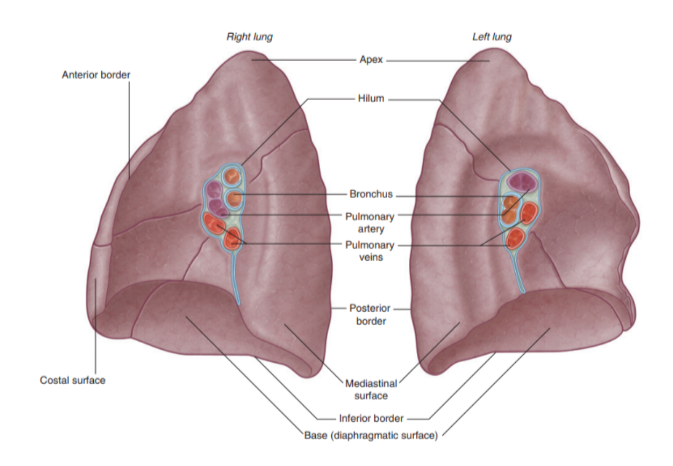

Landmarks recognizable in the lung

The base —

Situated on the diaphragm

The apex —

Projects above rib 1 & into root of neck

Costal surface —

Adjacent to ribs + Intercostal spaces

Mediastinal surface —

Lies against mediastinum anteriorly & vertebral column posteriorly — this surface contains the hilum

3 borders —

Inferior border —

Sharp, separates the base from the costal surface

Anterior border —

Sharp, separates costal surface from medial surface

Posterior border —

Smooth & rounded, separates costal surface from medial surface

We can also recognize certain indentations corresponding to surrounding structures

Root + hilum

The root —

A short tubular collection of structures attaching each lung to structures in the mediastinum

Covered in a sleeve of mediastinal pleura reflecting onto the lung surface as visceral pleura

Originates the pulmonary ligament — thin blade-like pleural fold projecting from the root towards the mediastinum, functioning to stabilize the position of the inferior lobe

The hilum —

The region outlined by this pleural reflection on the medial lung surface — where structures enter & leave

Structures we can find in each root & hilum —

Pulmonary artery

2 Pulmonary veins

Main bronchus

Bronchial vessels

Nerves

Lymphatics

The pulmonary artery is in most cases found at most superior portion of the hilum, while the pulmonary veins are inferior & the bronchi are posterior

On the side side however, the lobar bronchus to the superior lobe branches from the main bronchus in the root, unlike on the left where it branches in the lung itself superiorly to the pulmonary artery